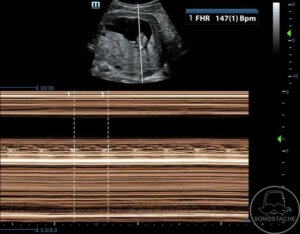

Case 8 – Fetal Heart Rate Assessment